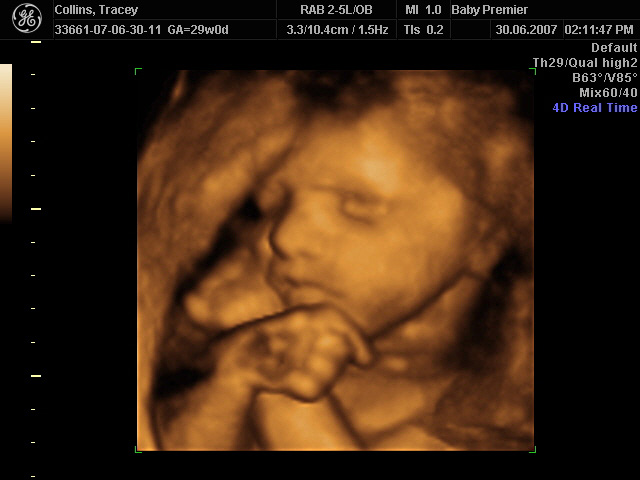

On 30th June 2007, we had a scan of our baby done in "4D" - fancy speak for a moving 3D image.

So sit back, relax, and enjoy Baby O in glorious 4D!